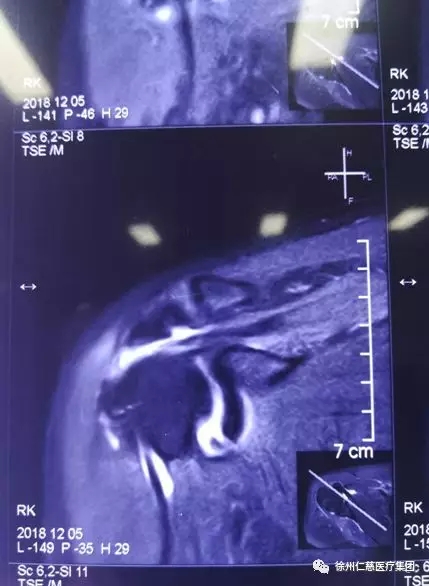

关节科郝亮医生检查发现,倪大姐的右肩袖损伤,右肩关节活动受限,影响日常生活,保守治疗无效,需手术修复。

术前片